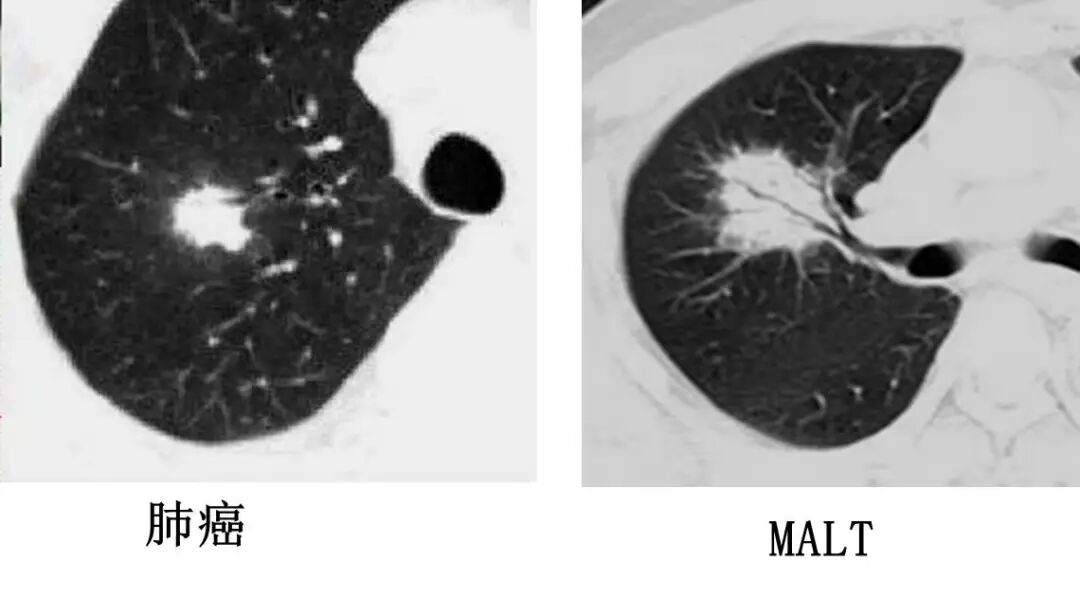

▼支气管肺癌

支气管肺癌

▶肺内单发结节或肿块

▶充气支气管管径正常,管壁破坏

肺粘膜相关淋巴瘤

结节、肿块,边缘模糊

充气支气管粗大、扭曲

肺内单发结节或肿块

支气管阻塞,充气支气管管径正常,管壁破坏